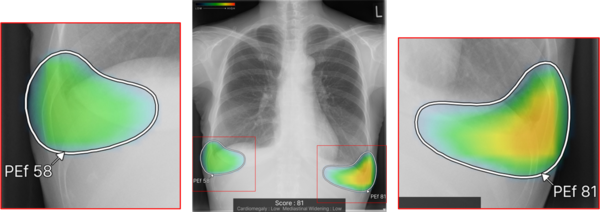

(2)ヒートマップ/輪郭表示機能

異常所見の存在可能性(確信度)を,青から赤へのグラデーションで示すヒートマップ表示について,多くの利用者から好評を得ている。一方,モノクロモニタを利用する一部の読影環境では,淡いヒートマップが確認しにくいという課題があった。新バージョンでは,異常所見の疑われる領域の表示方法として,「ヒートマップ表示」「輪郭表示」「ヒートマップと輪郭の併用表示」の3つの表示パターンが選択可能になった。これにより,各施設の運用環境に応じた最適な表示方法を利用できる。

ヒートマップ表示 |

輪郭表示 |

ヒートマップと輪郭の併用表示 |